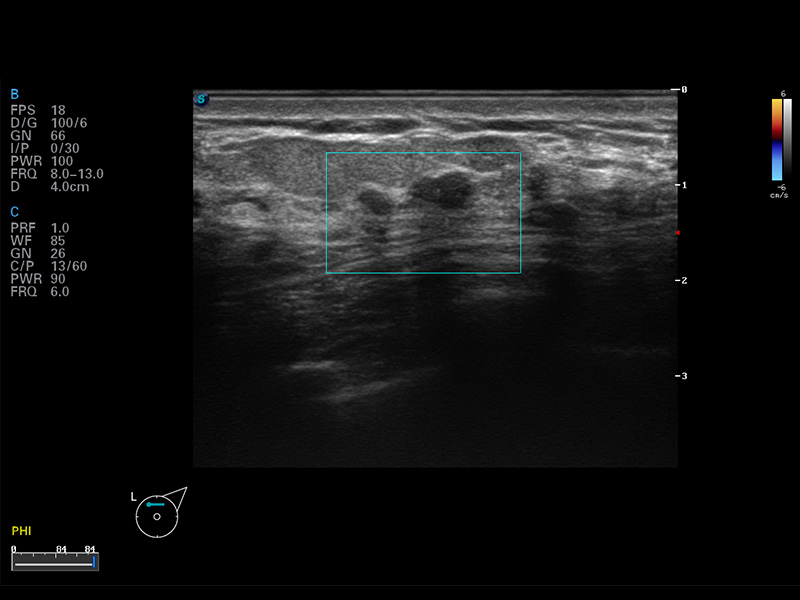

S8 EXP便携式彩色多普勒超声诊断仪是球速体育入口研发的高端全身应用型便携彩超。高通道的VIS平台融合可视化(Visual)、智能化(Intelligent)和人性化(Smart)的特点,配以球速体育入口自主研发生产的探头大家族,使您能够快速、准确的获得病人信息,提高工作效率的同时减轻疲劳。

成像技术

μ-Scan微米成像

谐波成像

空间复合成像